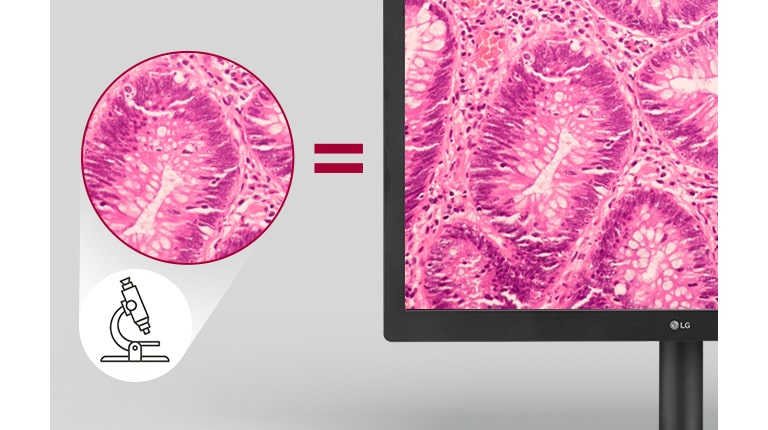

Clear Imaging

Pathology Mode

YES